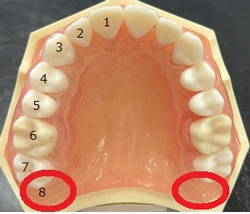

【親知らずとは】:第三大臼歯または智歯が正式名称

【はえる場所】:前歯から数えて8番目(1番奥)